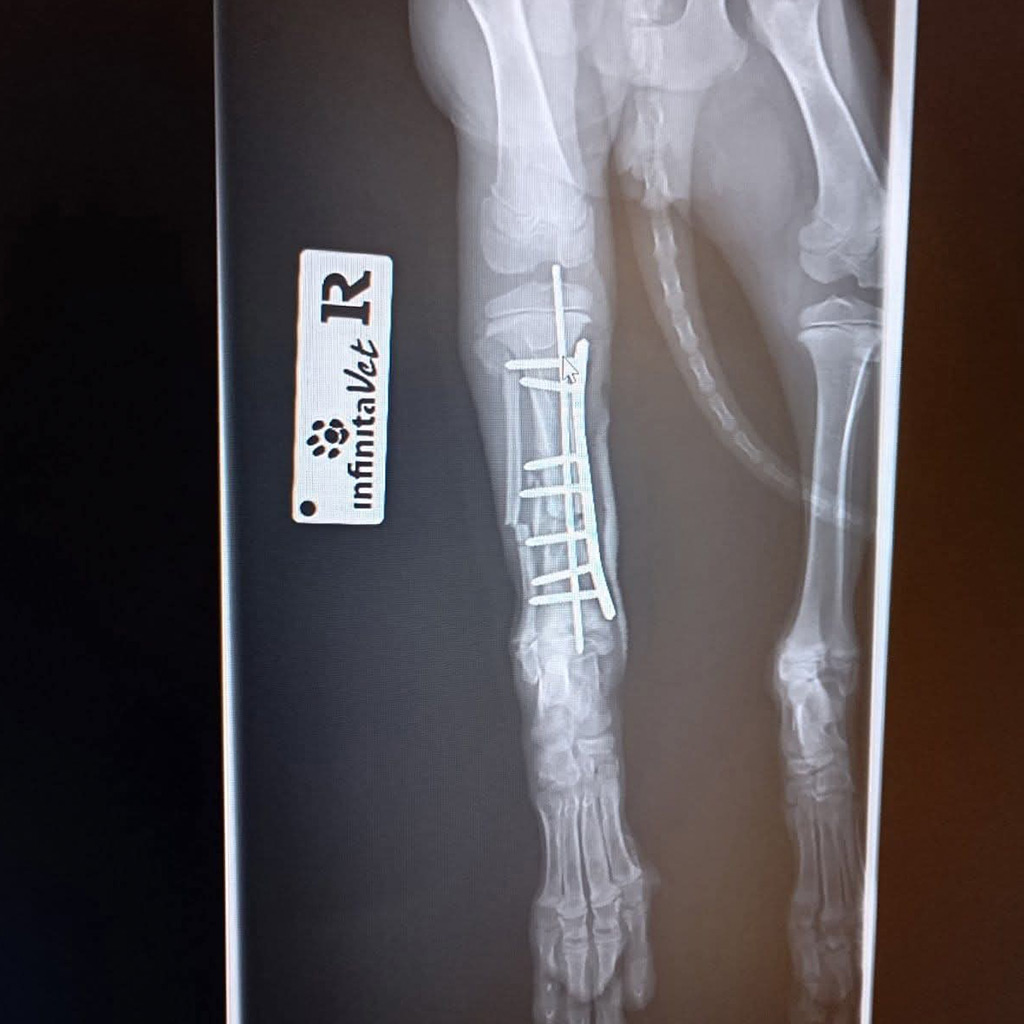

Das rechte Hinterbein wurde mit einer Platte stabilisiert und ist aktuell noch in einem schützenden Verband. Hier geht es zu Luca’s Video.

Zum Glück wurde Luca gefunden und sofort in eine Tierklinik gebracht. Dort folgte die erschütternde Diagnose: Ein Vorderbein und ein Hinterbein sind gebrochen. Die Röntgenbilder bestätigten das ganze Ausmaß ihrer Verletzungen.

Doch das Vorderbein ist so schwer verletzt, dass eine Operation dringend notwendig ist. Um eine stabile und dauerhafte Heilung zu ermöglichen, muss ein Metallimplantat eingesetzt werden. Nur so hat Luca die Chance, später wieder schmerzfrei zu laufen und ein normales Hundeleben zu führen.